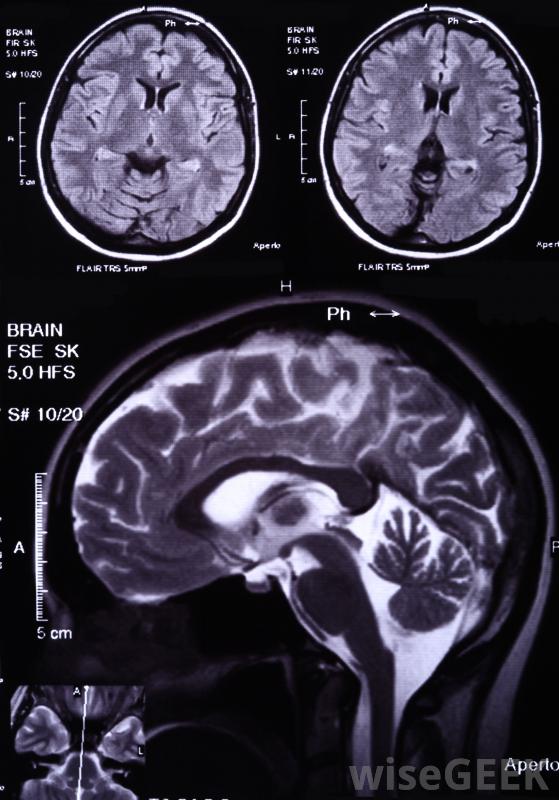

什么是白質疏松癥(Leukoaraiosis)?

腦白質疏松癥是一種血管密度降低的疾病,最常見于腦深部組織,這種情況往往發生在老年患者身上。患有白質疏松癥的人患腦血管疾病和癡呆癥的風險較高腦白質疏松癥患者患腦血管疾病和癡呆癥的風險增加,這種疾病不一定存在于患者身上,通常通過計算機斷層掃描(CT)或磁共振成像(MRI)來檢測到這種疾病。如果他們真的出現了,常見的癥狀包括身體各個部位的運動功能障礙、步態不均和認知障礙白質疏松癥通常通過老年患者的白質和大腦傳播,使他們更容易患癡呆癥腦白質疏松癥主要在腦白質內擴散,該區域由髓鞘軸突構成,軸突是神經系統的組成部分,白質是神經連接傳遞的物質吸煙的人患白質疏松癥的風險更高。一些最常見的白質疏松癥病因包括糖尿病、心臟病和高血壓。吸煙的人患白質疏松癥的風險更高這也是疾病。這些東西通過損傷大腦皮層下白質的血管而導致疾病。這種損傷通常是由于該區域在長時間內持續的緊張所導致的。白質疏松癥的病因可能包括心臟病。許多醫生會建議改變白質疏松癥患者的生活方式,以防止與此相關的其他疾病的發展這包括更高的心臟病發作和中風的風險。戒煙是對抗這種疾病最有效的方法之一。醫生也可能建議改變飲食、運動,并且服用常規劑量的阿司匹林。腦白質疏松癥通常會在腦部核磁共振掃描中發現醫生可能會向白質疏松癥患者推薦其他幾種檢查方法。其中一些用于跟蹤疾病的進展,而另一些則用于確定病情是否導致了其他問題,如該地區的血管阻塞。醫生通常會定期檢查膽固醇水平和血液病人的壓力。其他檢查可能包括頸動脈超聲,壓力測試,經顱多普勒檢查,或者心電圖檢查(EKG)。腦白質疏松癥患者可能會定期進行血液篩查以檢查膽固醇水平賓斯旺格病是腦白質疏松癥最常見的疾病之一,是一種小血管血管性癡呆癥,常在中風后出現,以精神衰退為典型特征,以奧托·賓斯旺格命名,他是1894年第一個描述這種情況的人,他的發現是腦白質萎縮會導致癡呆。醫生可以建議患有白質疏松癥的人改變生活方式。